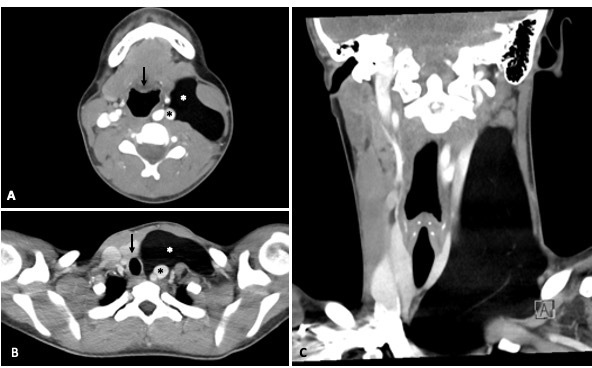

颈部及胸部CT扫描:左侧颈前三角区见一巨大脂肪密度肿块(3×6×15 cm),位于左颌下腺后方,胸锁乳突肌后内侧。该肿块从C3椎体延伸至上纵隔,导致咽部、喉部及气管向右侧移位。同时推移左侧颈内静脉和颈总动脉(未见明确血管受压征象),并对左侧甲状腺叶产生占位效应(图1)。

图1 脂肪瘤颈部CT扫描示意图。(A)轴位CT扫描显示脂肪瘤(白色星号)推移咽部(箭头)、左颈动脉及颈内静脉(黑色星号)。脂肪瘤位于胸锁乳突肌后内侧。(B)更低层面轴位显示脂肪瘤(白色星号)推移气管(箭头)、左颈动脉及颈内静脉(黑色星号)。(C)冠状位CT扫描显示脂肪瘤从C3椎体向上/向下延伸至上纵隔,同时再次观察到气管及血管向右侧移位。